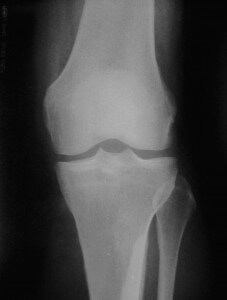

- На начальной стадии обнаруживаются краевые разрастания кости. При этом суставная щель на снимке не уменьшена. При осмотре обнаруживается частичное ограничение движений в суставе.

- При дальнейшем развитии патологии снимки показывают существенное разрастание костной ткани и сужение суставной щели. Больные жалуются не только на боли, но и на невозможность выполнять повседневную работу.

- Для запущенной стадии характерна деформация колена с уплощением. Разросшиеся края кости проникают в хрящ и суставную щель, что провоцирует полную потерю подвижности сустава.